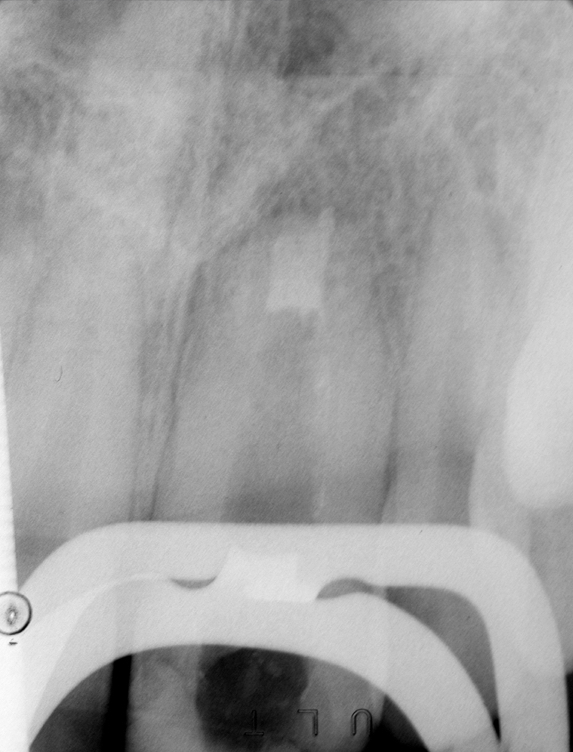

Clinical procedure: Regeneration of the endodontic pulp space is indicated for cases with very thin dentinal walls and an open apex that is more than 1 mm in diameter radiographically (Figure 4). Disinfection of the root canal system is performed using sodium hypochlorite irrigation followed by a triple antibiotic paste dressing that is left in place for 1 week. At the second visit, ethylenediaminetetraacetic acid (EDTA) is used to condition the dentin walls, which results in the release of growth factors, and bleeding is stimulated in the periapical tissues (where stem cells are located), with the aim of filling the pulp space with a stable blood clot, which would serve as the scaffold. MTA is then placed at the canal orifice in contact with the clot to protect it from coronal microleakage (Figure 5 and Figure 6). In time, the clot should be replaced with a reparative tissue of variable composition, and the root walls should continue to thicken due to the deposition of a dentin-like material on the pre-existing root dentin27,28 (Figure 7 and Figure 8).

Fig 4. Preoperative radiograph showing aggressive external root resorption and thin dentinal walls.

Figure 4

Fig 5. Working length confirmation.

Figure 5

Fig 6. Postoperative radiograph.

Figure 6

Fig 7. 1-year follow-up showing a healthy lamina dura and root development.

Figure 7

Fig 8. 3-year follow-up showing continued root development.

Figure 8